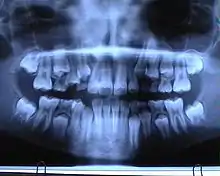

Ортопантомограма

Рентгенологічне дослідження в стоматології, або Ортопантомограма (OPG), також відома як «ортопанорама», «ортопантограма» та «панторекс» — панорамний рентгенівський знімок зубів, верхньої та нижньої щелепи.